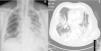

Un varón de 65años, ex fumador de 40paquetes/año, sin otros antecedentes, ingresó por disnea, tos con escasa expectoración mucosa y dolor de tipo pleurítico en hemitórax izquierdo de 5días de evolución, sin fiebre. Al examen físico destacaba taquipnea, a la auscultación pulmonar disminución del murmullo vesicular y crepitantes húmedos en el tercio inferior de ambos hemitórax, así como roce pleural en los dos tercios inferiores de hemitórax izquierdo. En la analítica sanguínea se evidenció leucocitosis (21.800/mm3), con neutrofilia (95%); proteína C reactiva, 34mg/dl. La radiografía posteroanterior mostró engrosamiento pleural izquierdo, patrón alveolointersticial bilateral, condensación en ambas bases pulmonares y borramiento del seno costofrénico izquierdo (fig. 1A). La tomografía axial computarizada (TAC) de tórax a las 48h demostró extensa condensación alveolar bilateral con derrame pleural de predominio derecho, varias colecciones pleurales organizadas izquierdas y adenopatías inflamatorias (fig. 1B). Ante la presencia de reactantes de fase aguda sanguínea y el cuadro radiológico se inició tratamiento antibiótico con betalactámicos y levofloxacino intravenoso, y tras la TAC se realizó fibrobroncoscopia, que fue compatible con proceso supurativo agudo, y toracocentesis, que mostró exudado purulento, con un pH de 7,22; 22.730 leucocitos/mm3; 73% neutrófilos; 27% linfocitos; glucosa, 110mg/dl; LDH, 2.371U/l, y proteínas, 4,5g/dl. Se instauró drenaje torácico derecho con instilación de 100.000U.I. de uroquinasa y emisión de 500ml a lo largo de 3días. El derrame pleural izquierdo organizado se trató de manera conservadora al encontrarse escasa cámara pleural. Los antígenos de Legionella en orina fueron positivos, y a los 7 días se observó crecimiento de L. pneumophila en el líquido pleural sembrado en medio BCYEα y confirmado posteriormente por PCR-STB (sequence-based typing). Las demás pruebas (cultivo de broncoaspirado, catéter telescopado protegido, hemocultivos) fueron negativas. La evolución del paciente fue favorable, con remisión progresiva de la clínica y de los infiltrados pulmonares.